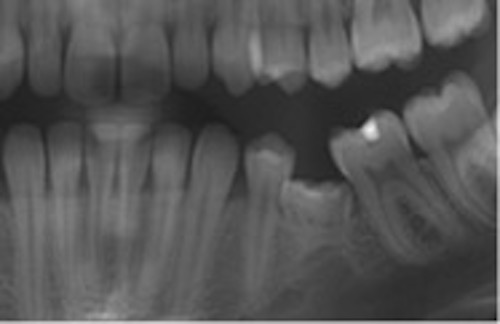

Infraocklusion av tänder innebär att tänderna befinner sig under ocklusalplanet hos angränsande tänder. Avståndet kan variera från någon millimeter till att ocklusalytan är under gingivakanten eller inte ens syns i munnen (1-4). I de flesta fall erupterar alla primära molarer upp till ocklusal kontakt med motstående tänder. Senare börjar en del hamna i infraocklusion och ibland blir de även ankylotiska.

I sällsynta fall kan primära molarer ses i infraocklusion redan i 3-4 årsåldern, men mest frekvent är infraocklusion i 9-10 års ålder (2). Omkring 14 % av barnen i dessa åldrar har en eller flera primära molarer i infraocklusion. Det förekommer dubbelt så ofta i underkäken som i överkäken. Infraocklusion av primära molarer förekommer ofta hos barn som även har andra tand- eller eruptionsavvikelser så som agenesi av premolarer, små eller tappformade överkäkslateraler, ektopisk eruption av överkäkens första permanenta molarer och retinerade överkäkshörntänder (5-8).